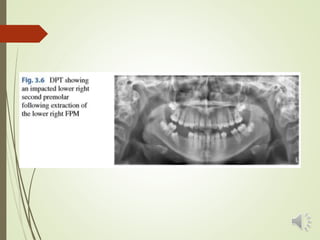

 A DPT is indicated to review the presence and position of all

the developing permanent teeth.

 The prevalence of hypodontia affecting the second

premolar teeth and the second permanent molar teeth has

been reported as 1–3% and <1%, respectively.

 The presence or absence of the third molar teeth is also of

relevance.(absent in 20–30% of European pop.)

 Also, calcification of the third molars has been reported to

commence between the age of 7 and 10 years.